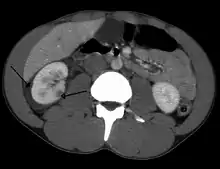

A large hematoma (closed arrow) of the left kidney (open arrow)

The kidneys may also be injured; they are somewhat but not completely protected by the ribs.[6] Kidney lacerations and contusions may also occur.[13] Kidney injury, a common finding in children with blunt abdominal trauma, may be associated with bloody urine.[13] Kidney lacerations may be associated with urinoma or leakage of urine into the abdomen.[4] A shattered kidney is one with multiple lacerations and an associated fragmentation of the kidney tissue.[4]